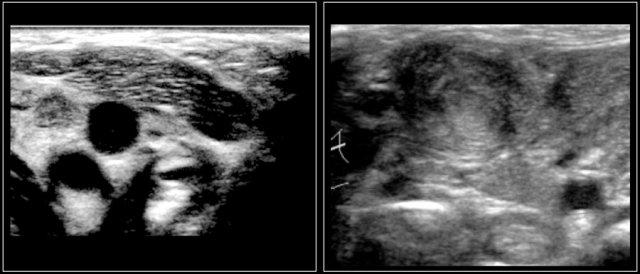

Hình ảnh của một bé trai mười bốn tuổi với khối sưng không đau ở cổ bên trái.

Siêu âm cho thấy nhiều hạch bạch huyết giảm âm phóng to, không có rốn hạch tăng âm.

Đây là một bé trai mười bốn tuổi khác với tình trạng sưng không đau ở cổ bên trái.

Siêu âm cho thấy nhiều hạch bạch huyết to.

Continue with the MR and PET/CT…

Hình ảnh STIR mặt phẳng coronal cho thấy các khối hạch bạch huyết bệnh lý tương tự như trên PET-CT.

The diagnosis was Hodgkin’s lymphoma.